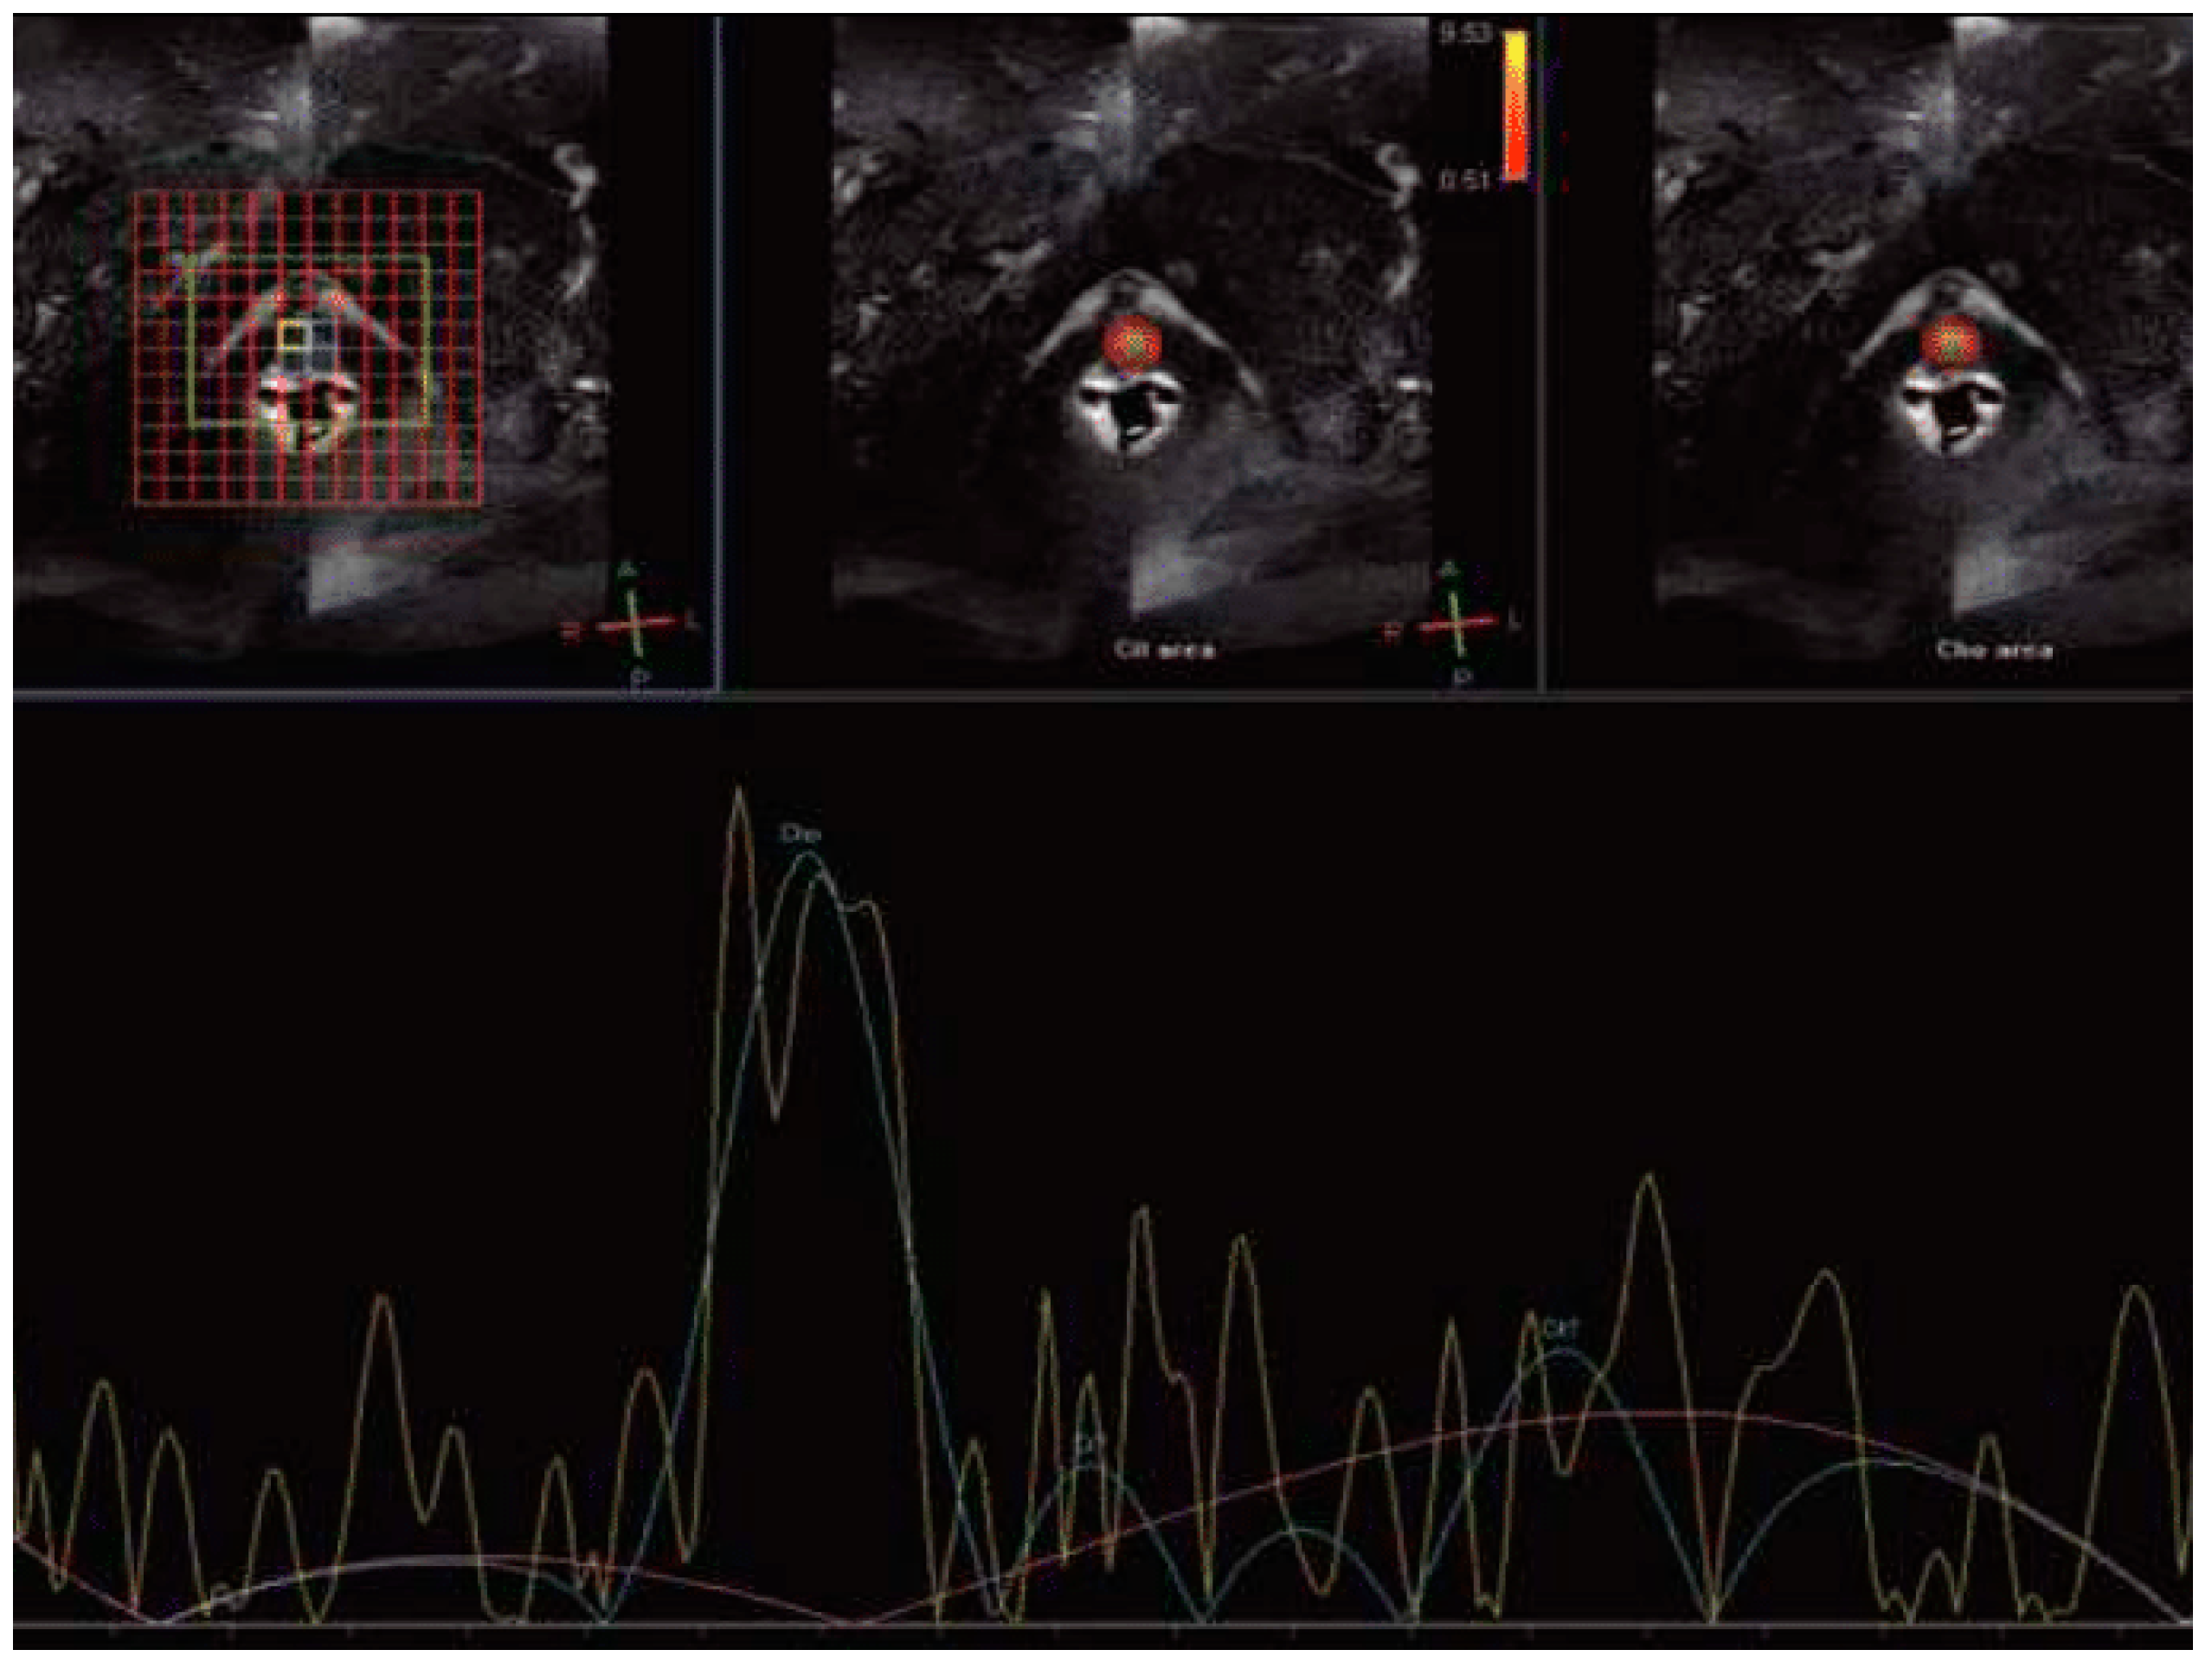

Magnetic Resonance Spectroscopy (MRS)

| Liao et al., 2018 [23] | review | Magnetic Resonance Spectroscopy (MRS) | Increase concentration of choline and citrate. | 69% (95% CI: 0.58–0.78) | 86% (95% CI: 0.79–0.92) | Indicative biomarkers of prostate energy metabolism tumor membrane cellular activity | Long image acquisition High cost Low sensitivity |

- Deal, M.; Bardet, F.; Walker, P.-M.; de la Vega, M.F.; Cochet, A.; Cormier, L.; Bentellis, I.; Loffroy, R. Three-dimensional nuclear magnetic resonance spectroscopy: A complementary tool to multiparametric magnetic resonance imaging in the identification of aggressive prostate cancer at 3.0t. Quant. Imaging Med. Surg. 2021, 11, 3749–3766. [Google Scholar] [CrossRef] [PubMed]

- Asuncion, A.; Walker, P.M.; Bertaut, A.; Blanc, J.; Labarre, M.; Martin, E.; Bardet, F.; Cassin, J.; Cormier, L.; Crehange, G.; et al. Prediction of prostate cancer recurrence after radiation therapy using multiparametric magnetic resonance imaging and spectroscopy: Assessment of prognostic factors on pretreatment imaging. Quant. Imaging Med. Surg. 2022, 12, 5309. [Google Scholar] [CrossRef]